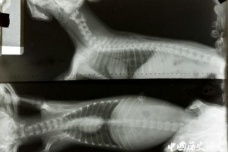

具有透视功能的女孩是谁为什么会有透视功能能看到什么